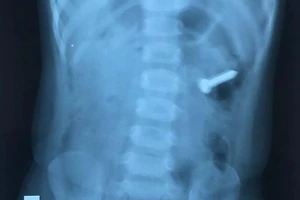

Bé gái 2 tuổi nuốt chiếc đinh ốc xoắn dài 3 cm